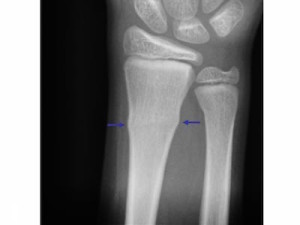

Buckle fractures

Another fracture often seen in kids. This time it's caused by pressure going down through a bone, causing it to 'buckle' in on itself, not unlike crushing a can. Here we're just looking for a bulging in the cortex of the bone. These 'bulges' can be tiny!

Image source